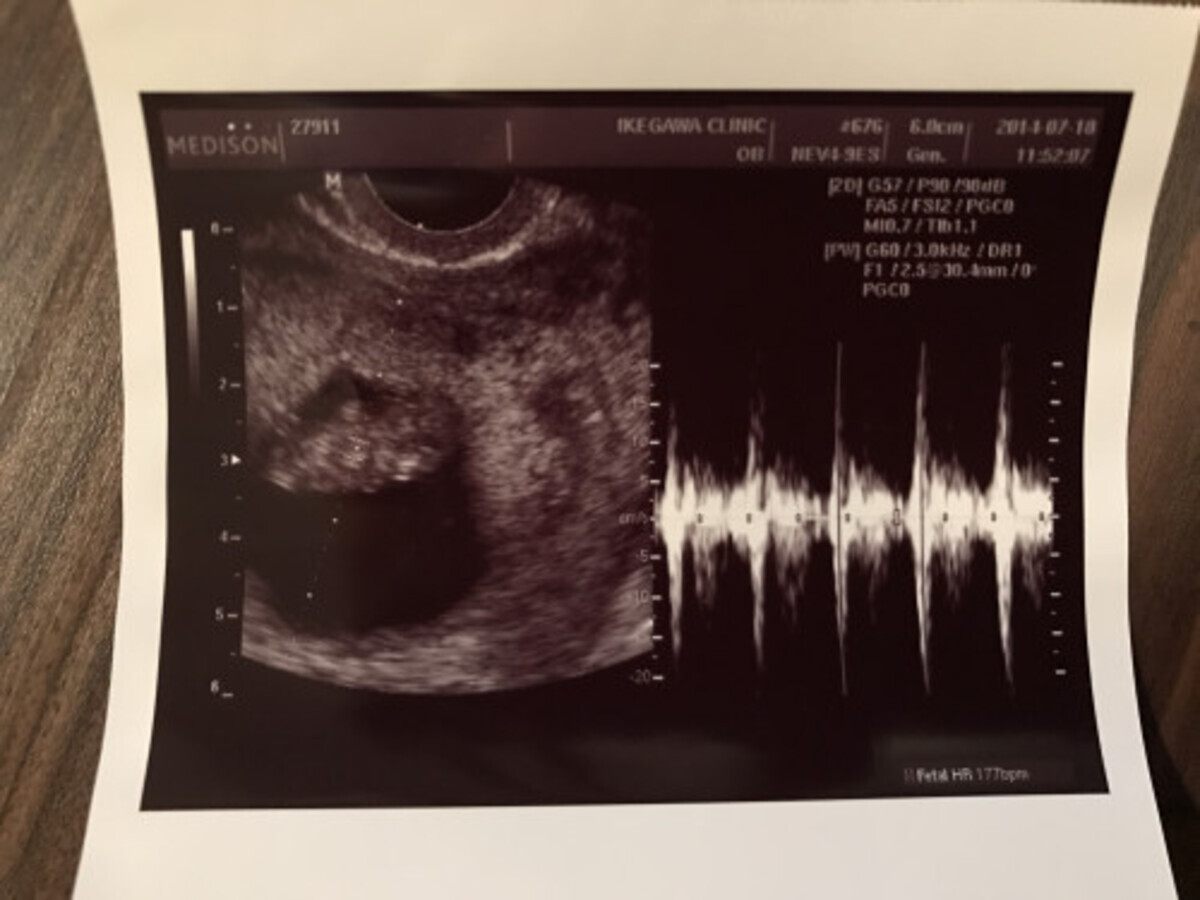

Nt指摘後の妊娠記録。 33歳 一年ほどの妊活を経て一人目の妊娠 21/1 検査薬で陽性→心拍確認。 2/9 妊婦検診にてntがあると指摘。出生前診断を勧められる。 2/22 胎児ドッグと絨毛検査で異常なし、陰性 ここからはnt指摘後の記録を残します。Apr 22, 21 · 画像を確認致しました。 妊娠検査薬に判定線が薄く出ていますが、正常妊娠かどうかは判断できません。 妊娠検査薬の結果判定においては、血液混入で擬陽性反応が出る場合があります。Nov 29, 14 · どうか、お知恵を貸してください。タイトル通り、性行為後1週間で検査薬に陽性反応が出ました。ですが、主人が私の浮気を疑い、俺の子ではないと信じてもらえません。もちろん、主人以外に心当たりなどありません。最終生理が10月17日。9

Jan 24, 19 · 妊娠検査薬で陽性反応が出てから、妊娠確定までにはいくつかのステップがあります。その一つが子宮内に「胎嚢(たいのう)」が確認されること。胎嚢って何? 胎嚢が確認できないのはどんなとき? 妊娠確定の第一歩「胎嚢」について、産婦人科医の新村朋美先生に詳しく伺いました。Feb , 17 · #妊娠検査薬陽性に関する一般一般の人気記事です。''おすすめ 妊娠検査薬 使いやすさ 感度 比較bt7''47歳 妊娠 義母に妊娠報告''d34 高温期16日目☆ついに、妊娠検査薬を‥‥''私が感じた妊娠超初期症状と生理前との違い''画像あり妊娠検査薬の陽性反応(デイビッド・クリアブNov 28, 15 · hcg注射を使用した場合は妊娠検査薬がhcg注射の成分に反応して、本当は妊娠していないにも関わらず陽性反応を出してしまう、偽陽性が出てしまうことがあります。hcg注射と妊娠検査薬についてのお話しです。